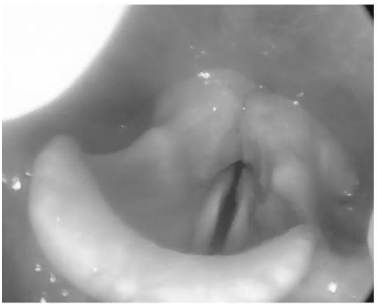

Considere o seguinte caso clínico: paciente do sexo feminino, evoluindo com dispneia leve e estridor após cirurgia de tireoidectomia total. Em videolaringoscopia realizada no primeiro dia pós-operatório, foi visualizada laringe com redução de movimentação de pregas vocais bilateralmente com redução do espaço glótico, conforme imagem. A qualidade vocal da paciente se encontrava pouco alterada. Enunciado 3175275-1